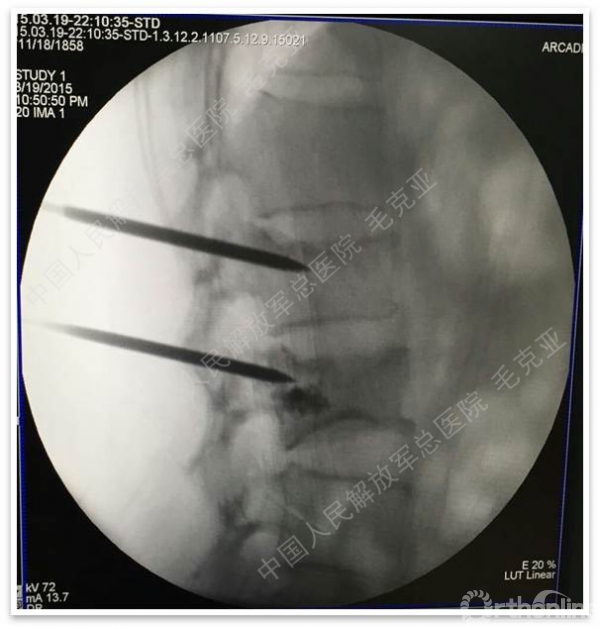

导语:随着社会老龄化的不断加速,骨质疏松性椎体压缩骨折作为一种普遍存在的老年骨科疾病已经成为现今骨科界的一个热点话题。传统的保守疗法治疗效果不佳,而现有的椎体增强技术又具有多种风险和缺陷。针对这种现状,中国人民解放军总医院毛克亚教授提供了一种新的解决方法。